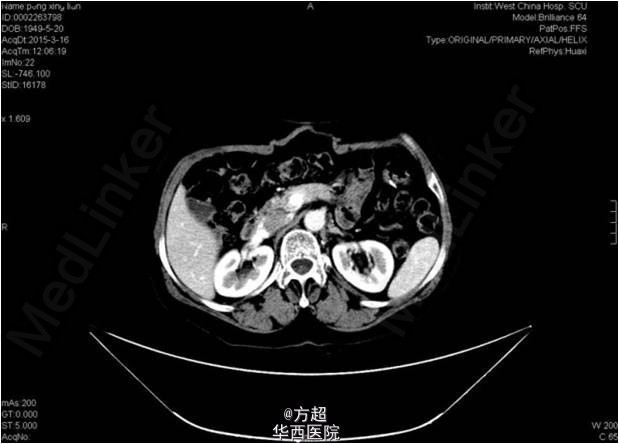

入院查体:肿瘤相关指标未见明显异常;腹壁原手术切口处活动性包块,大小12*11cm,质软,可触及肠管;腹部CT可见腹壁缺损,大小约8cm,腹腔脏器未见异常,未见直肠癌复发及转移征象。